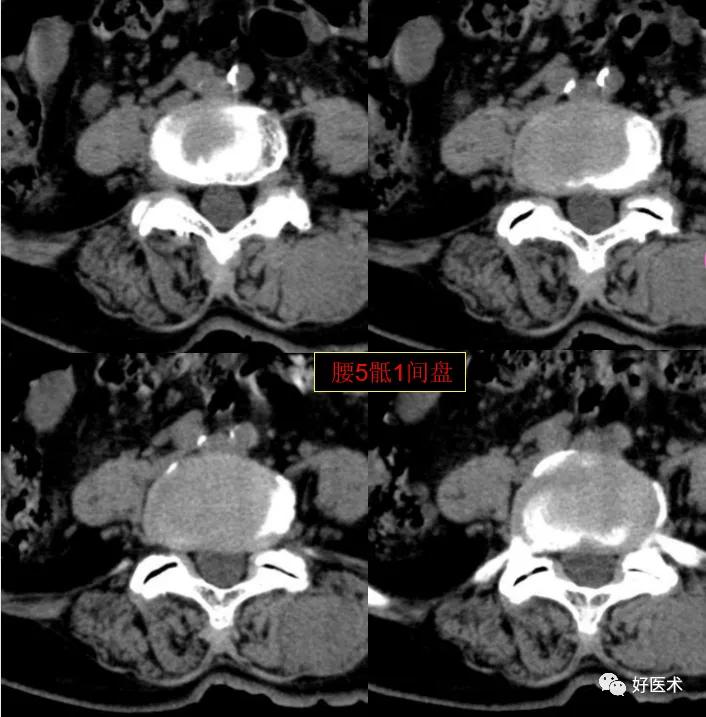

CT图像,腰椎常规采用序列扫描,腰椎体2层,腰间盘4层,层厚2.5mm,一般扫描范围包括腰2--骶1椎体及所属间盘。

腰5骶1间盘膨隆,双侧椎小关节积气